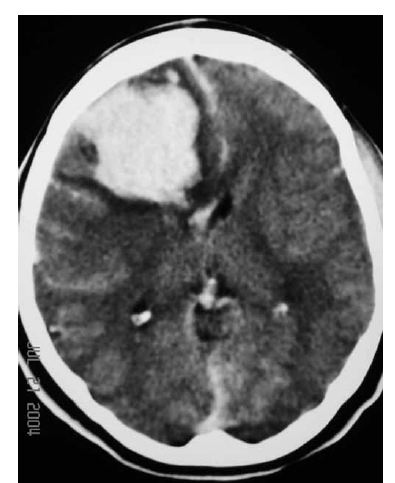

Uma mulher de 29 anos de idade teve sua gestação interrompida com 35 semanas, mediante parto cesariano, por ter apresentado quadro compatível com a doença hipertensiva específica da gravidez. No quinto dia de pós-operatório, apresentou importante dor de cabeça seguida de crises convulsivas; na avaliação laboratorial, foram atestadas plaquetopenia e alteração da função hepática. Ela foi levada à unidade de terapia intensiva, onde o plantonista observou hemiparesia esquerda e solicitou uma tomografia de crânio sem contraste, que é reproduzida abaixo.

Para essa paciente está contraindicada a punção lombar para alívio da cefaleia.